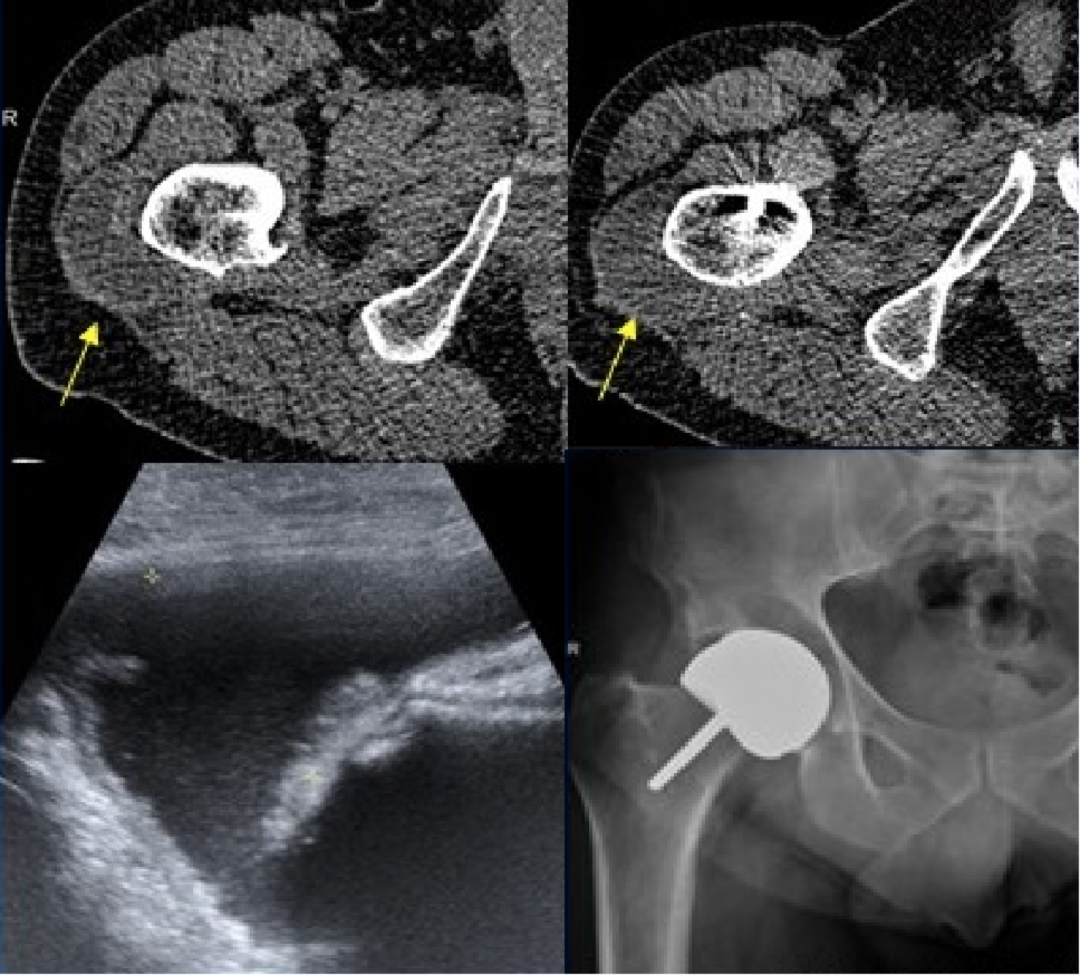

4.骨溶解:

发生率 5%~9%,与透亮线不同,地图样透亮区是由假体相关的骨水泥、金属或聚乙烯颗粒诱导的组织炎症反应所致(颗粒病)。

右侧髋臼及耻骨支骨质溶解吸收,关节周围团块状软组织肿块,围绕股骨头及股骨颈